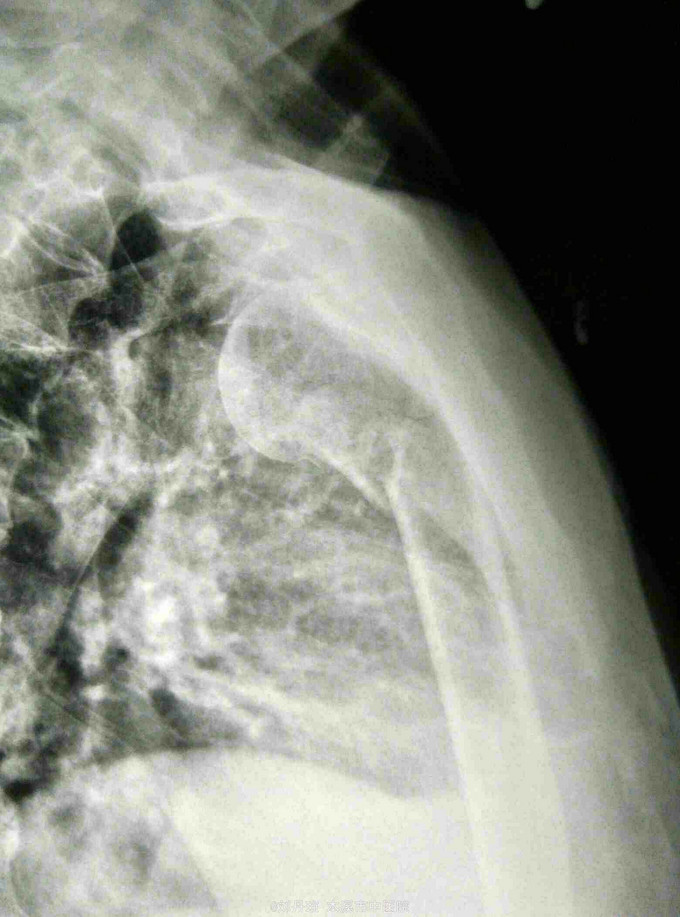

患者男60岁。主诉:左肩刺痛,活动受限2小时。 病史:患者2小时前散步时不慎摔倒,左肩刺痛, 活动受限。伤后由朋友送入我院。

左肩部畸形、肿胀明显,外科颈部压痛阳性,左肩部功能障碍。DR: 左肱骨近端粉碎骨折,分解为四部分,移位明显。

诊断:左肱骨近端粉碎骨折 治疗:手法整复,夹板固定。接骨丹口服。

随访1年。此四部分骨折,肱骨近端四个解剖部分完全分离,肱骨头移向后方,肱骨头血运破坏严重,容易发生缺血坏死。